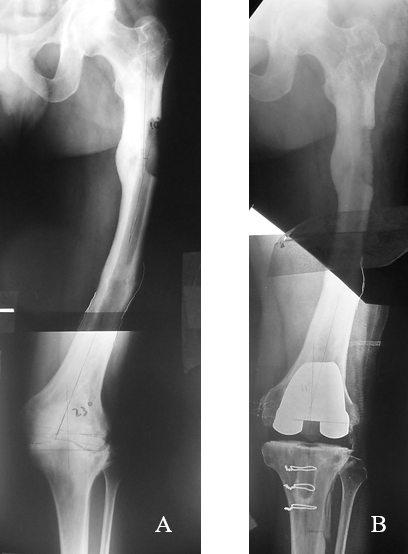

Figura 2: Empleo de radiografías convencionales superpuestas para la medición del eje. a) Paciente de 47 años, que presenta deformidad medio diafisaria en dos segmentos del fémur izquierdo por secuela de fractura. Desalineación coronal femoral de 18° en varo y eje anatómico de 23° de valgo. b) Diagnóstico de genu valgo artrósico y movilidad articular de 10º a 40º, se realizó el ATR obteniendo un eje final de 7° de valgo. Se realizó la osteotomía de la tuberosidad anterior de la tibia para facilitar el acceso quirúrgico.

Figura 3: : a, b) Paciente de 79 años que sufrió una fractura diafisaria bilateral de fémur. c, d) Consolidación viciosa con desplazamiento medial del segmento óseo distal de 3 cm en el fémur derecho, y desvío coronal de 8° de valgo en el izquierdo; recurvatum de 8° en el fémur derecho y 9° en el izquierdo. e, f) ATR bilateral no simultáneas.